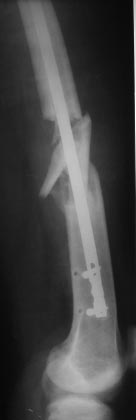

Уважаемые коллеги, наконец пациент явился на повторный осмотр, через два с половиной месяца после операции.

Был рекомендован постельный режим в течение одного месяца, после контрольная Р-графия и потом решить, но со слов б-ного постельный режим 10 дней, ходьба при помощи костылей и палочки еще дней 20, и уже более полутора месяцев ходит без палочек, самостоятельно, с полной нагрузкой. При осмотре ось бедра правильная, активно поднимает ногу, укорочения нет, пальпаторно безболезненный, амплитуда движений в коленном суставе около 80гр.: 80/0/5. (якобы коленный сустав не разрабатывал из-за боязни боли).

Рекомендована активная разработка движений.

Выложил Р-снимки и фото.

С уважением Абдурашид.